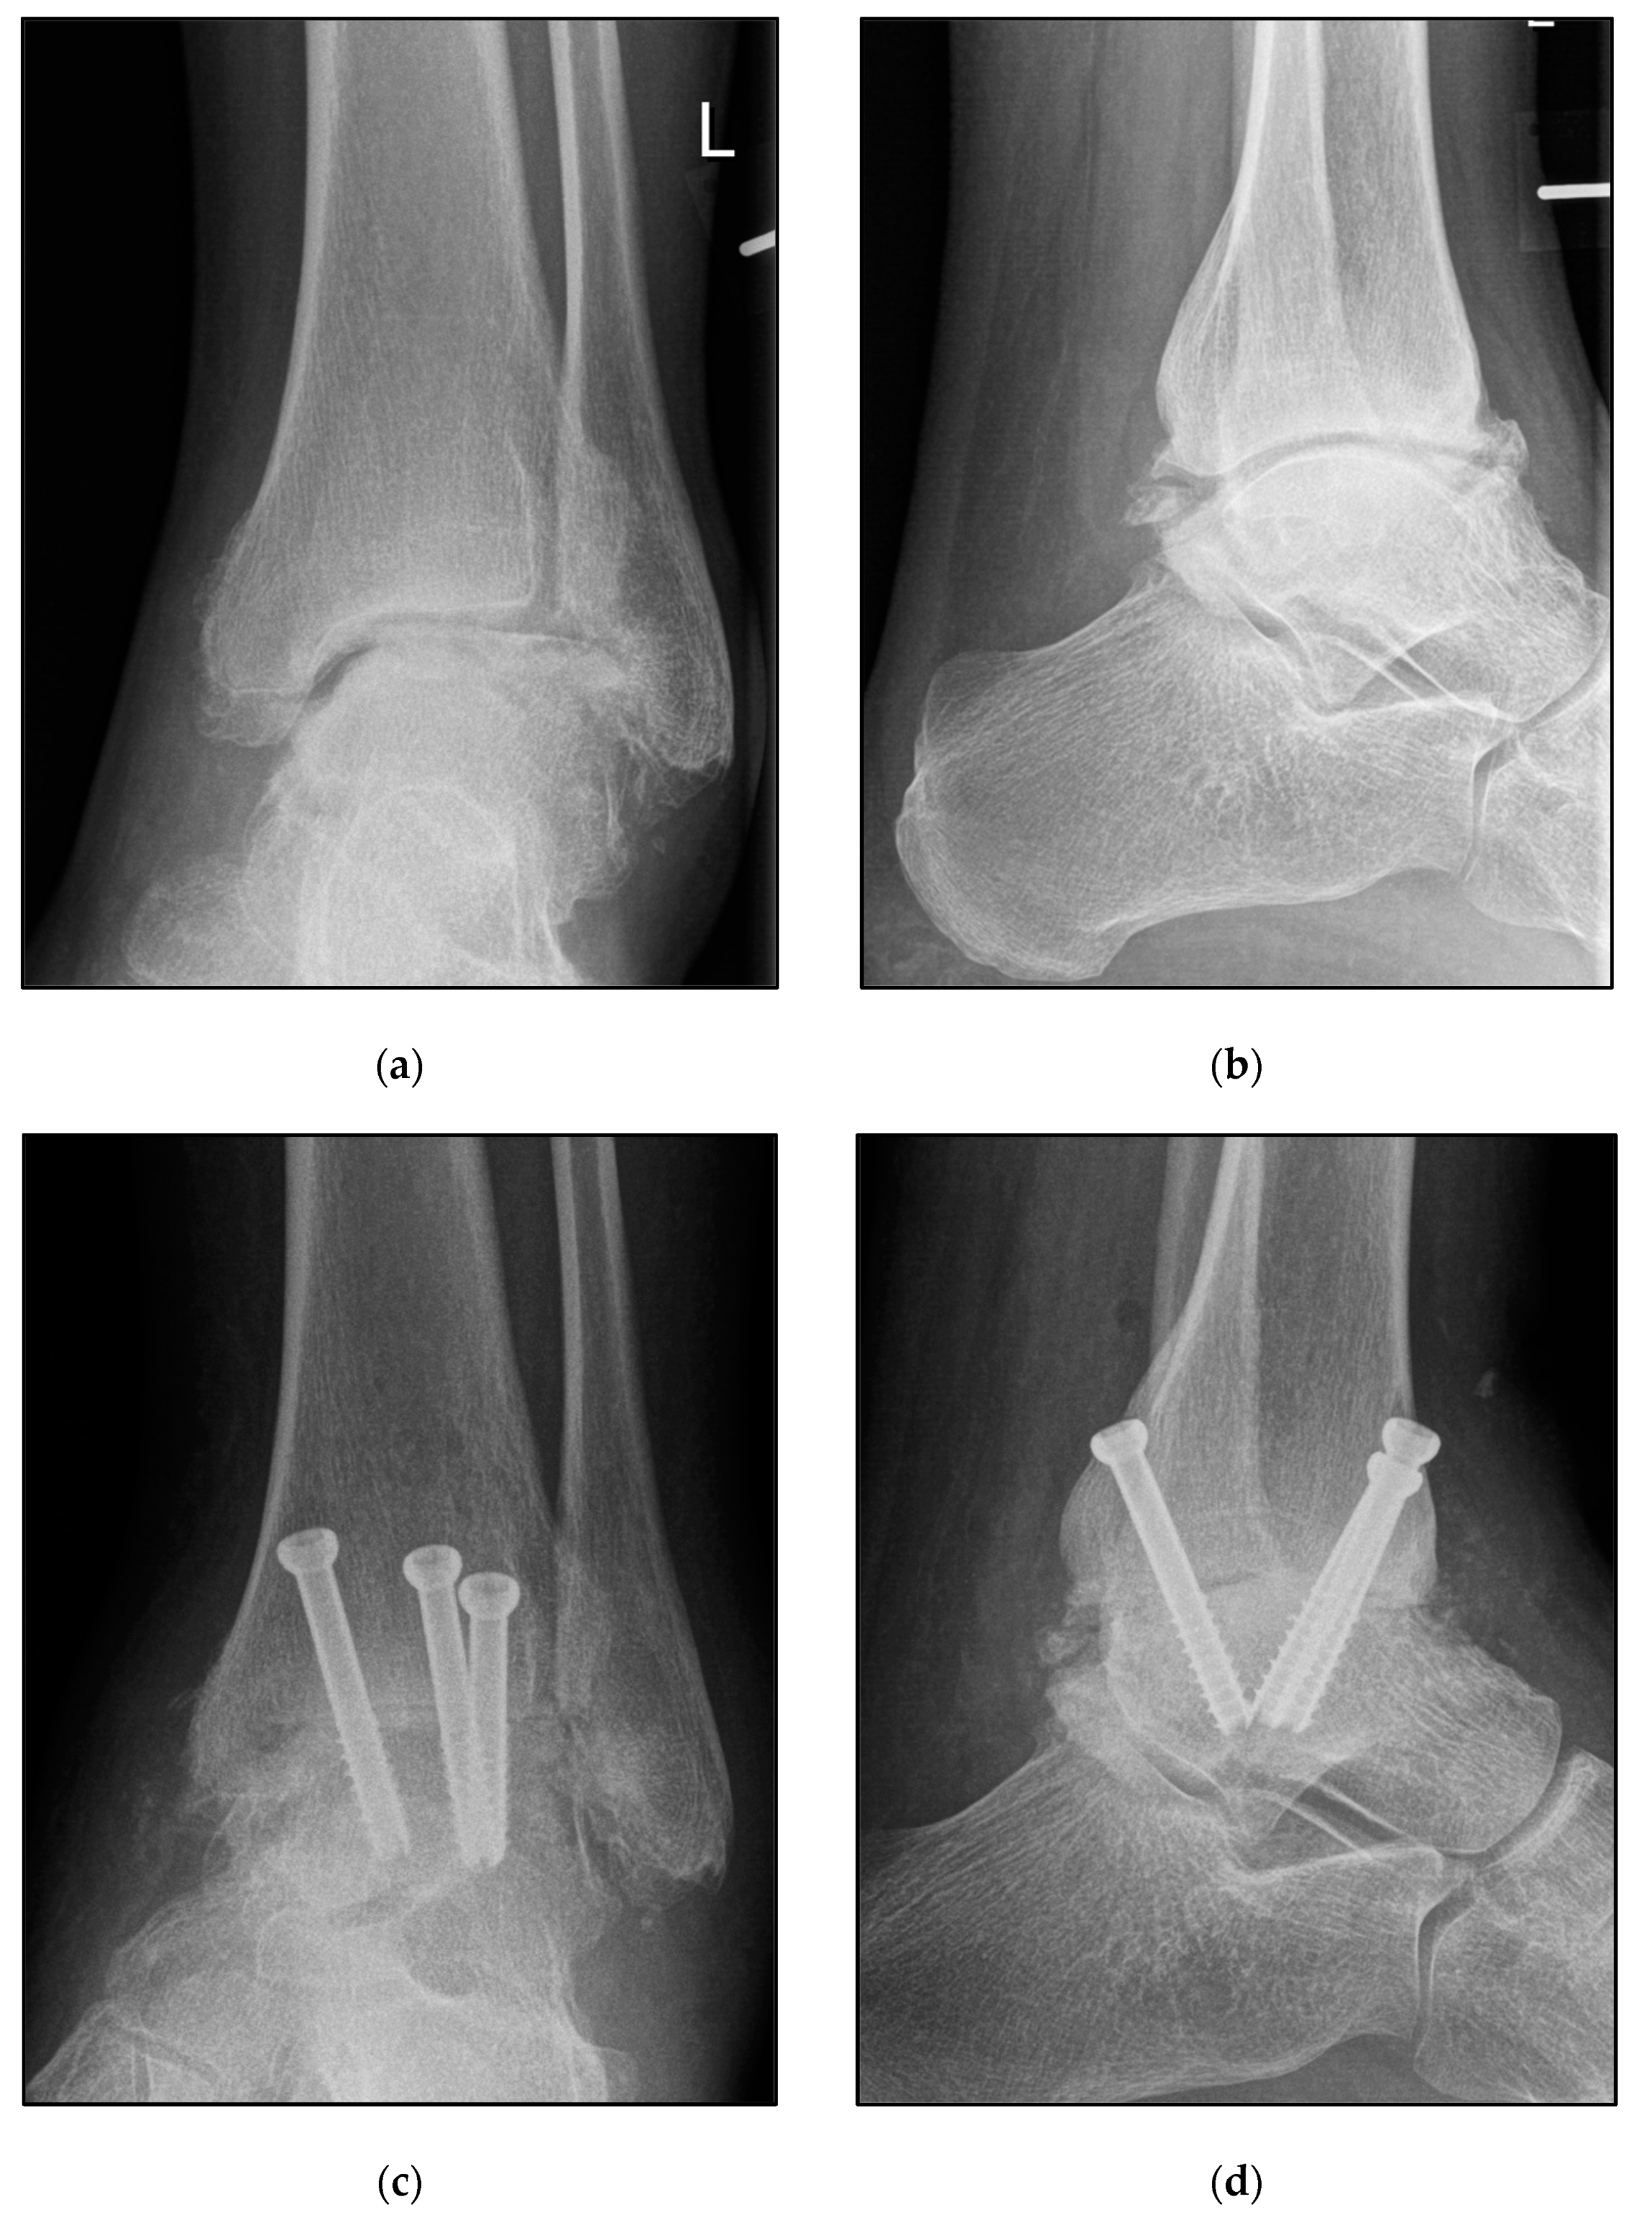

2.3. Surgical Procedures